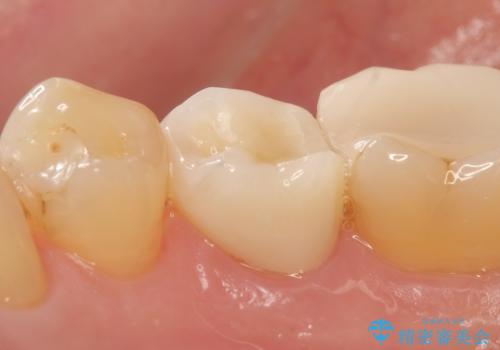

- 右下でものを咬むと痛むので診て欲しいといらっしゃった方の症例です。

検査の結果右下5番目の歯の神経が死んでいたため、根管治療を行った後、オールセラミッククラウンによる補綴を行いました。